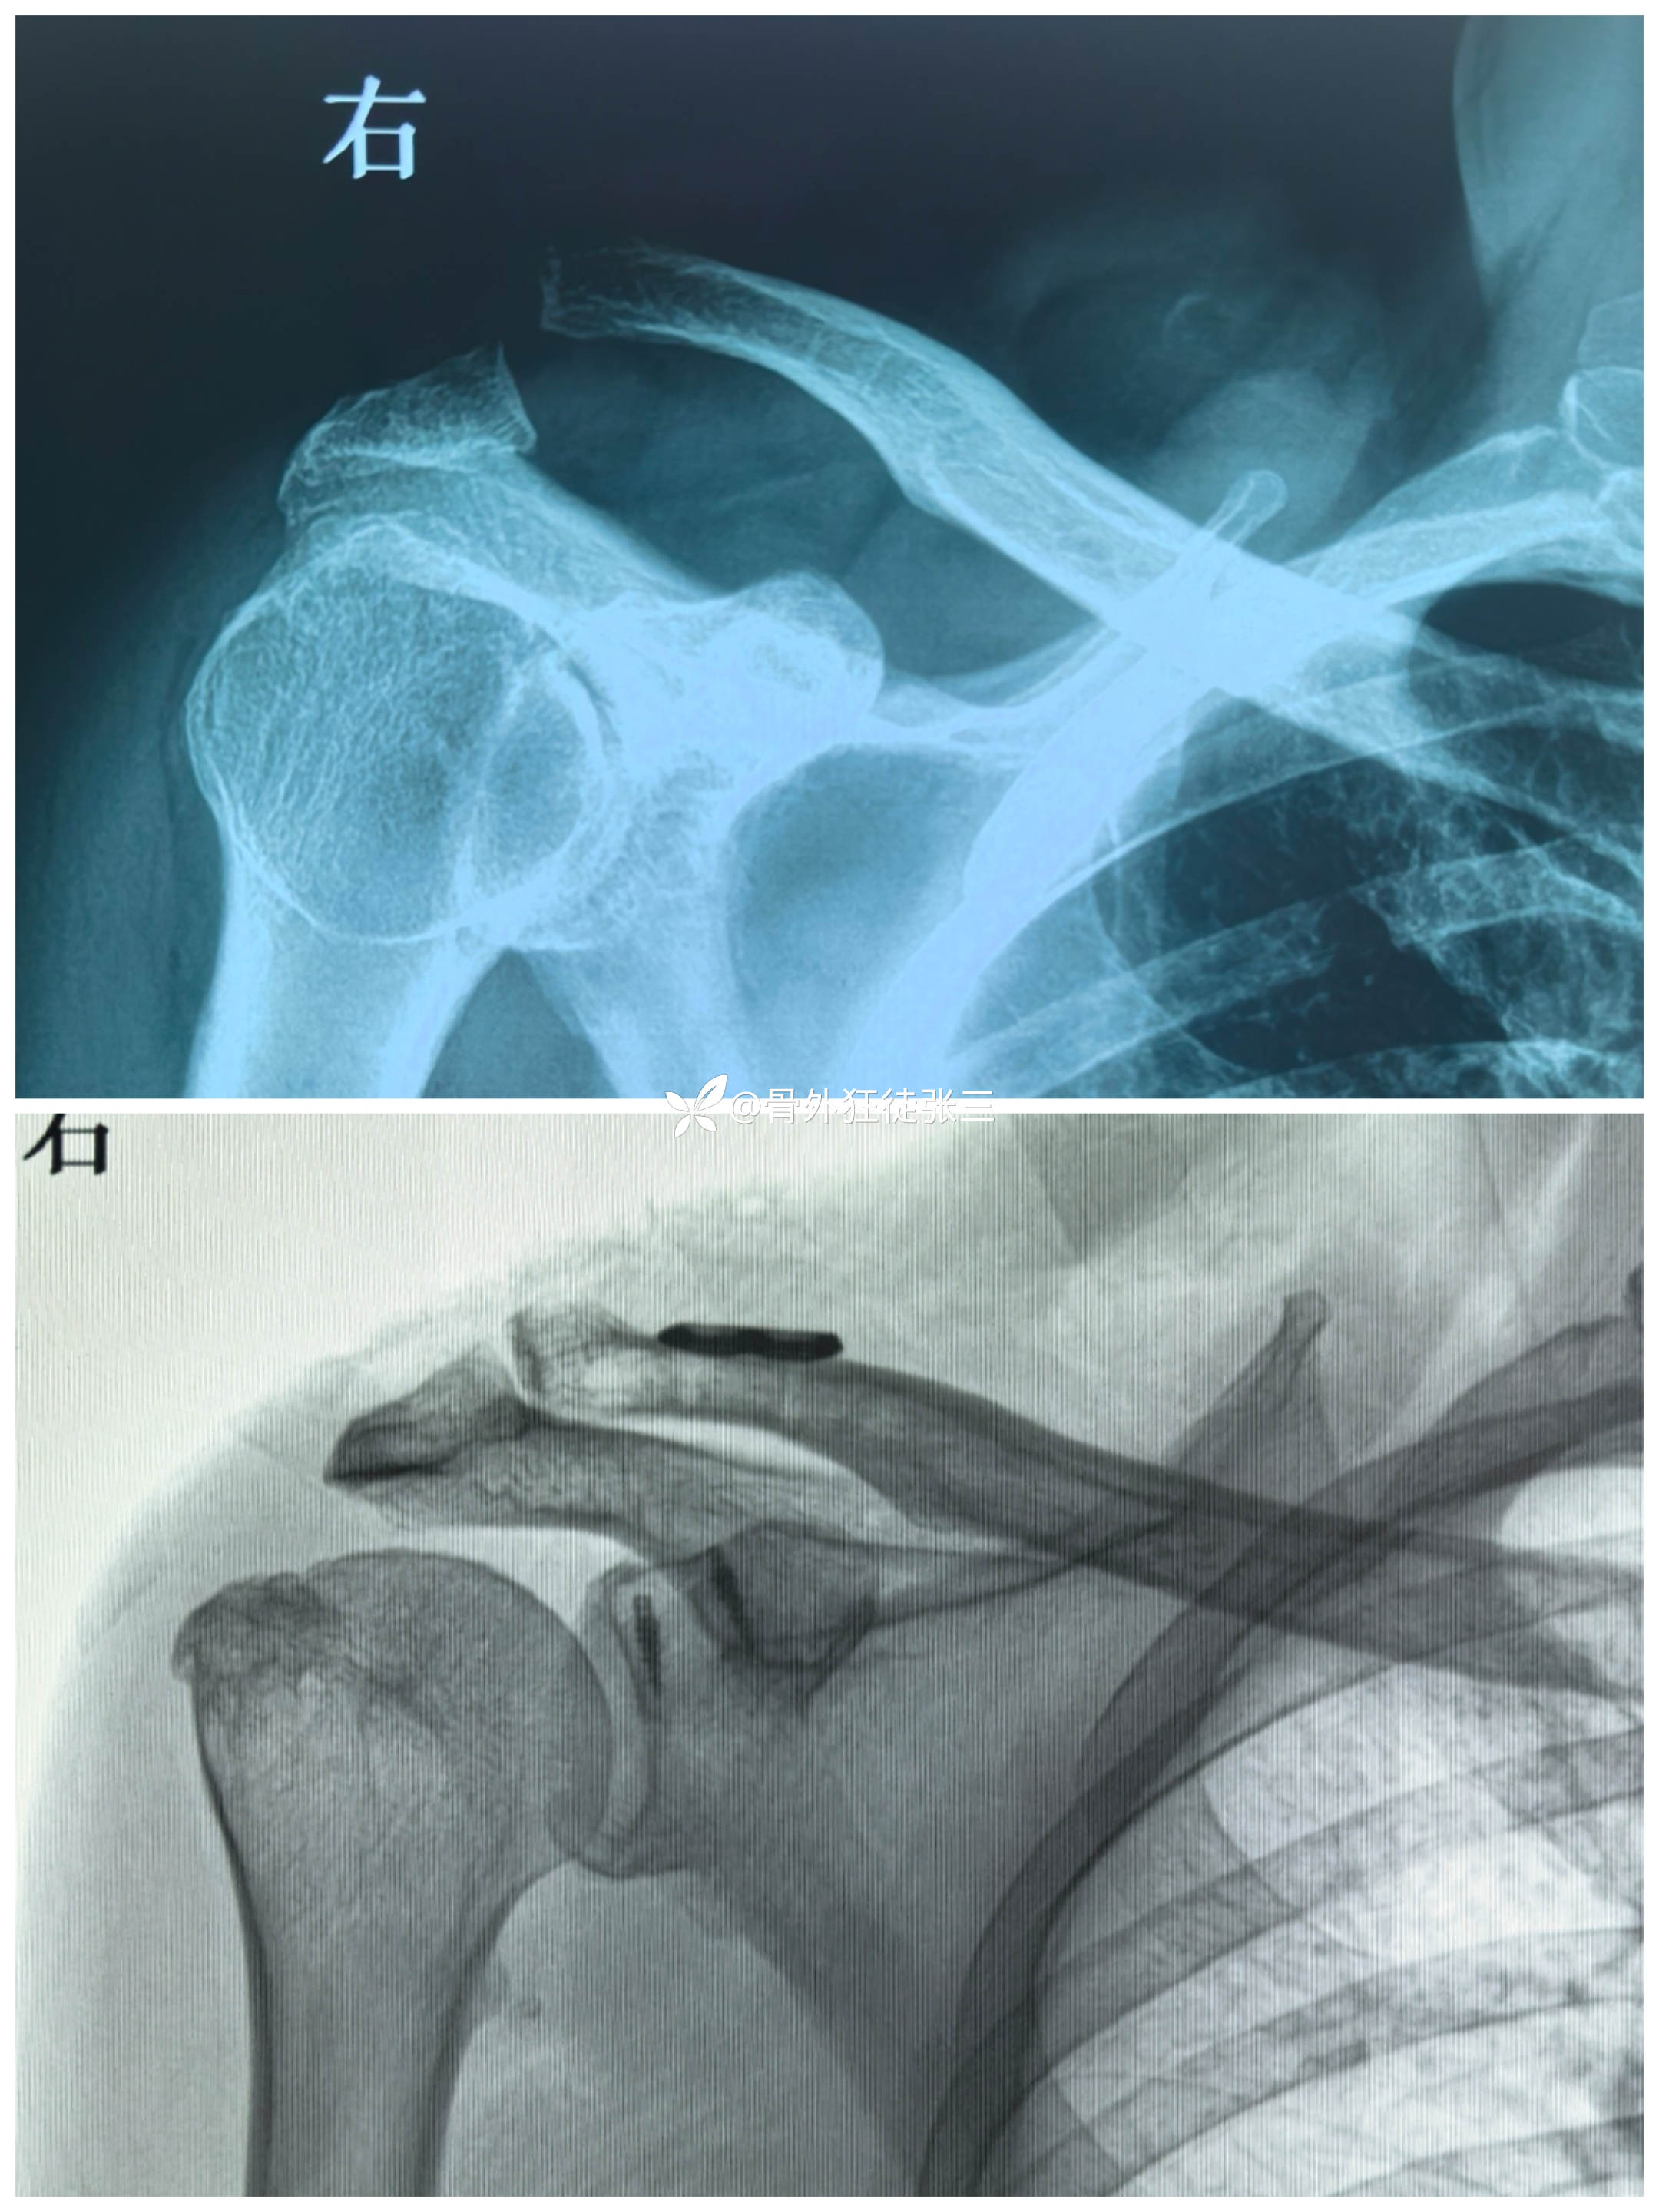

主诉:摔伤右肩关节致疼痛、活动受限1天。

辅助检查:

临床诊断:

右肩锁关节脱位(Tossy分型III型)